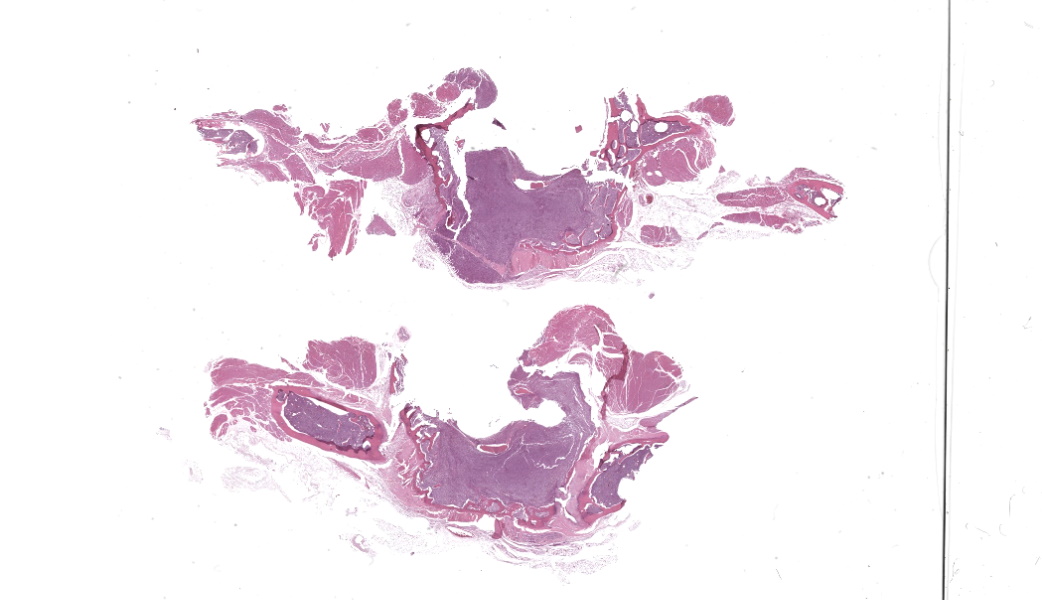

Associated with the vertebral body and the ventral aspects of the pedicles of T11 and protruding into the vertebral canal was a 0.6 cm long, soft, light purple grey, bilobed mass that surrounded and compressed the local segment of spinal cord. With examination of the external surface, an approximately 1.4 cm long segment of the regional spinal cord was streaked white, red, and dark red (hemorrhages). After formalin fixation and decalcification, the T11-L1 vertebrae was sectioned serially. The cut surfaces of the T11 vertebral body and portions of the pedicles were expanded and replaced by a poorly demarcated, soft, shiny, white tissue inconsistently mantled by an irregular brown rim that filled the medullary cavity with loss of the trabecular architecture. The regional cortical bone was irregular and multifocally thinned.

In addition, the spleen was severely enlarged (95.6 g; 6.8% of the body weight) with dozens of randomly distributed sharply demarcated, pinpoint to 0.6 cm in diameter, oval to spherical, soft, white foci and nodules.

The slide also contained several key osseous features, including resting and reversal lines, microfractures, reactive fibrosis, and numerous osteoclasts. All of these are consistent with an aggressive, lytic bone process. Although not present on the H&E slide, the contributor provided some excellent gross and additional histologic images that showed compression myelopathy of the affected area of thoracic spinal cord, serving as a correlation to the pathogenesis of the clinical presentation in this case.

The gross image of marked a markedly enlarged spleen with multifocal, pale tan nodules prompted a strong reminder from Dr. Alves that this pattern should raise suspicion for necrotizing splenitis across species lines. The marked splenic enlargement in this species is a common finding in older ferrets and typically associated with extramedullary hematopoesis (noted by the contributor in this case).